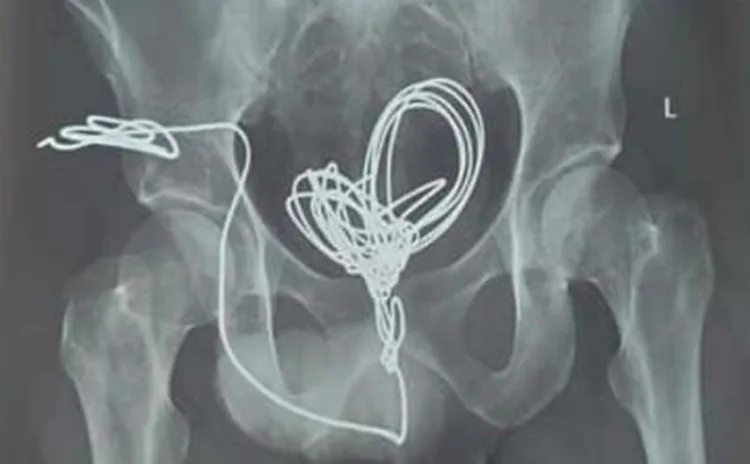

തിരുവനന്തപുരം: തിരുവനന്തപുരം സ്വദേശിയായ 25കാരന് മൂത്രനാളിയിലൂടെ സ്വയം കുത്തിക്കയറ്റിയ മൂന്ന് മീറ്ററോളം ഇലക്ട്രിക് വയര് മൂത്രസഞ്ചിയില് നിന്ന് ശസ്ത്രക്രിയയിലൂടെ പുറത്തെടുത്തു. തിരുവനന്തപുരം മെഡിക്കല് കോളേജ് ആശുപത്രി യൂറോളജി വിഭാഗത്തില് രണ്ടര മണിക്കൂറോളം നീണ്ട ശസ്ത്രക്രിയയിലൂടെയാണ് പല കഷ്ണങ്ങളായി മുറിച്ച് ഇലക്ട്രിക് വയര് പുറത്തെടുത്തത്. തീവ്രപരിചരണ വിഭാഗത്തില് കഴിയുന്ന യുവാവ് സുഖം പ്രാപിച്ചു വരുന്നതായി ആശുപത്രി അധികൃതര് അറിയിച്ചു.